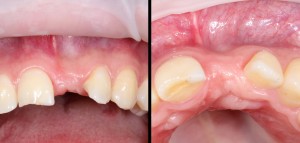

1

С одной стороны, мы можем правильно позиционировать нужный имплантат в существующем объеме костной ткани. С другой стороны, существующая атрофия костной ткани представляет из себя не просто эстетический дефект, но и повлияет на функциональность и долговечность протетической конструкции.

Следовательно, можно установить имплантат и «нарастить» вокруг него необходимые объемы костной ткани. Что мы и делаем:

4  8  9

с неплохим, в общем-то, результатом:

16